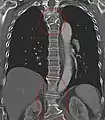

Block vertebrae of the cervical spine (vertebrae 4 and 5). Probably based on degenerative or inflammatory changes.